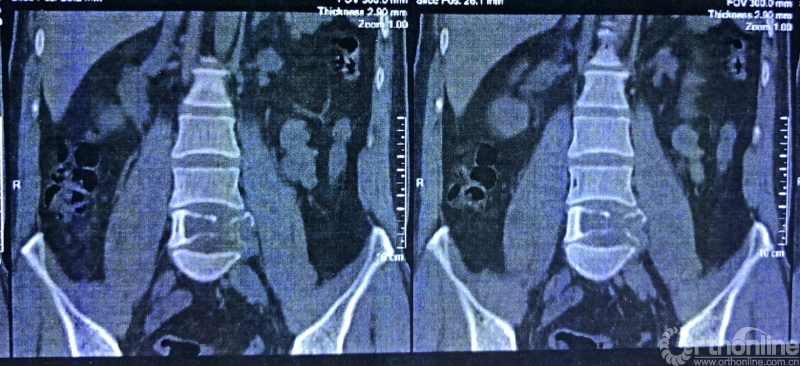

就诊前CT

通过对患者详细的身体检查、穿刺活检和综合评估后,确诊患者是腰椎骨巨细胞瘤,第五腰椎破坏70%以上,邻近软组织也有破坏。这种肿瘤属于交界性的有恶性倾向的良性肿瘤,若不彻底切除,患者疼痛会逐渐加剧,甚至因骨质坍塌而瘫痪,若肿瘤细胞转移更会危及生命。若是能在早期尽快彻底、完全地切除肿瘤及被侵蚀椎体,病人才很可能完全战胜肿瘤。

术前CT三维重建